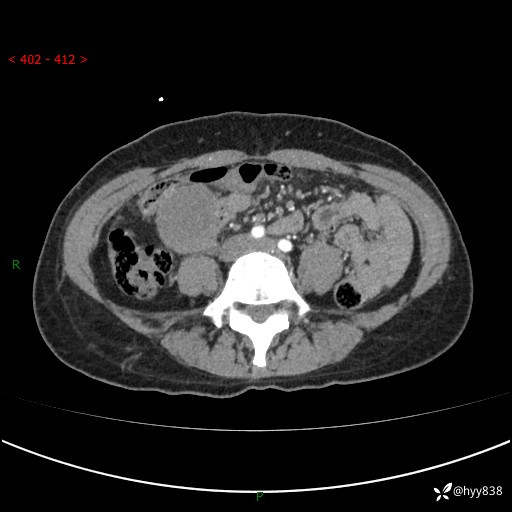

年轻女性,发现腹腔肿物1周。圆圆的肿物,诊断有难度---结果公布~

现病史:患者自诉于1周前无明显诱因出现剑突下间断性隐痛,尚可忍受,不向其它部位放射,无恶心呕吐、腹泻便秘等不适,于当地市第二人民医院就诊,行CT结果示:1.右中腹占位,间叶组织来源可能2.小肠梗阻3.盆腔积液4.腹腔积液5.副脾6.肝囊肿;于荆州二医行抗炎,抑酸,护胃,补液等对症支持治疗;患者病情好转,今为求进一步诊治,遂来我院门诊就诊,门诊以“腹腔肿瘤”收入院。 起病以来,患者精神、睡眠、饮食一般,大小便正常,近期体力体重无明显改变。

腹部CT增强(外院平扫)